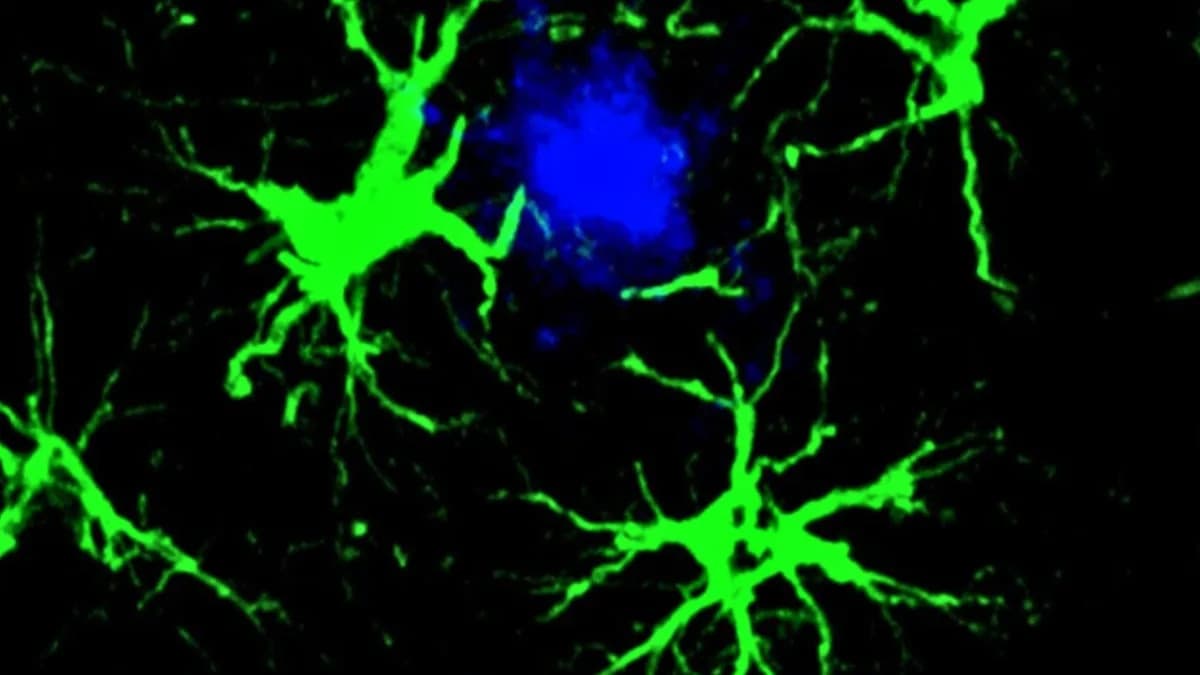

Novi injekcioni sistem iz UCSF‑a preprogramira CAR‑T ćelije direktno u telu — jedna doza lečila leukemiju kod miševa

Naučnici sa UCSF‑a razvili su dvočestični injekcioni sistem koji preprogramira T‑ćelije protiv raka direktno u telu koristeći CRISPR‑Cas9 i virusolik nosač sa CAR‑genom. U humanizovanim miševima jedna doza je u...